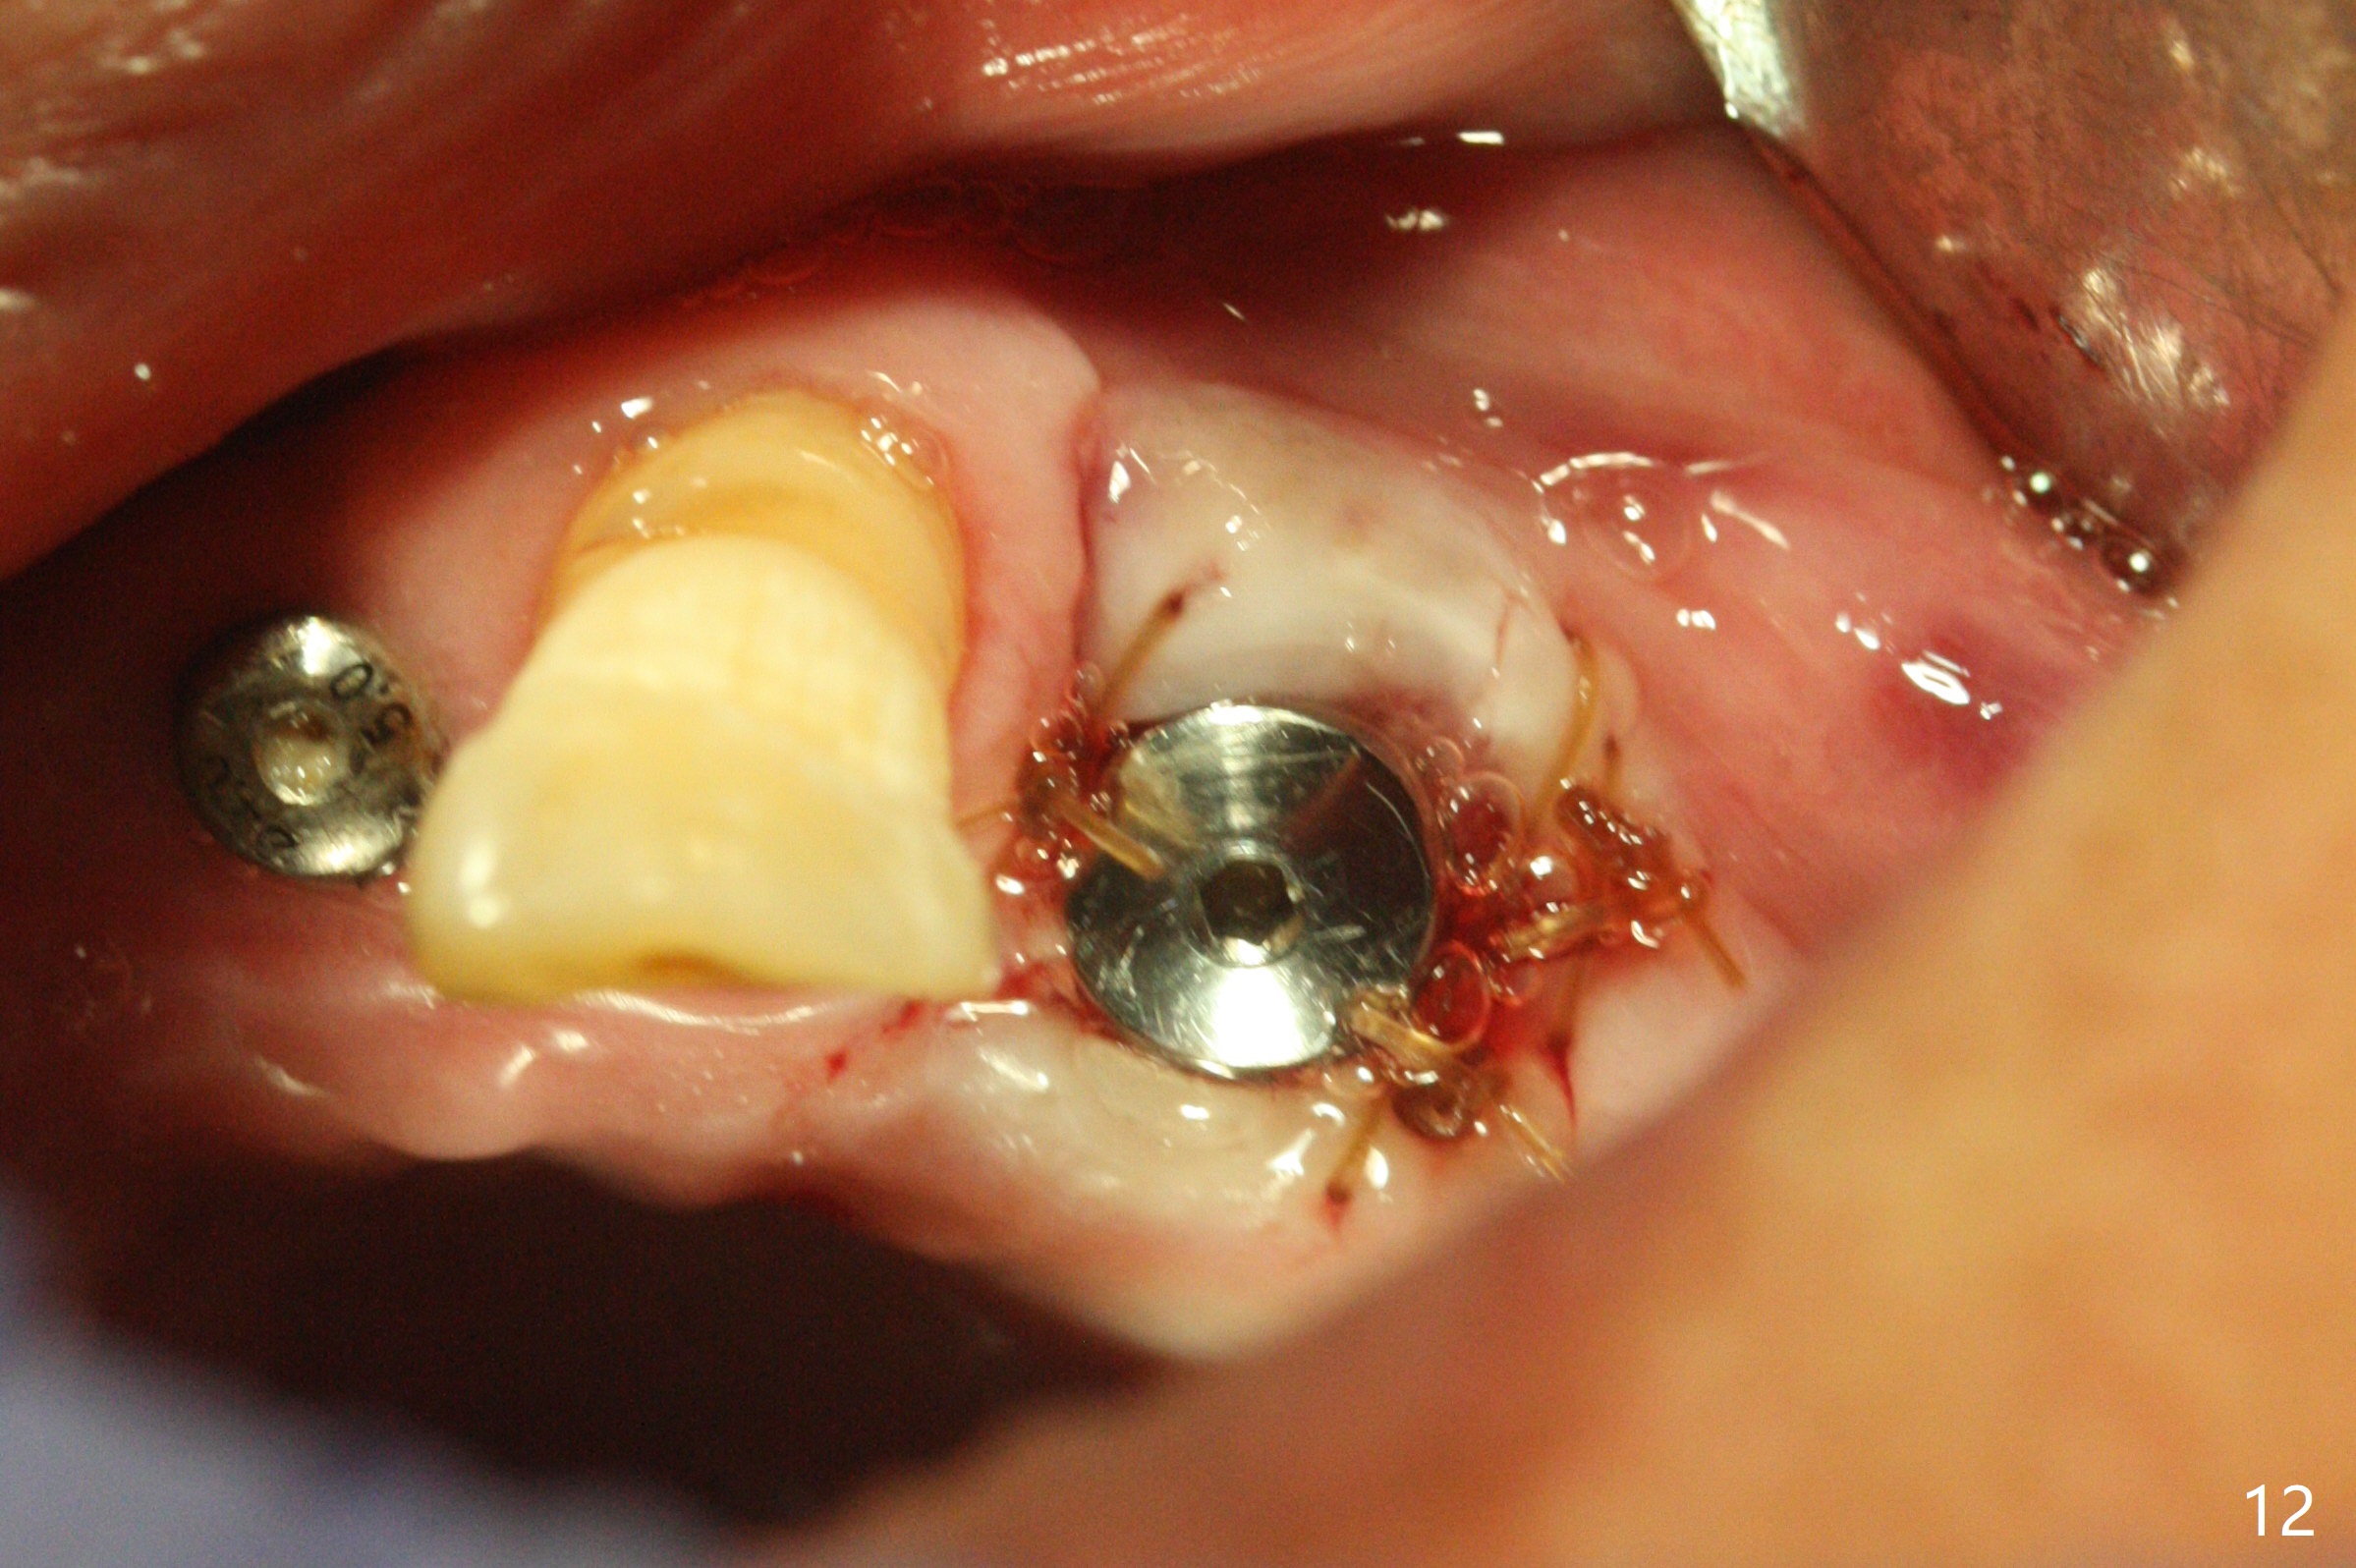

Five months post implant removal and bone graft, incision is made at #12. Osteotomy is being done with guide until 3.0x7.3 mm drill with 1 O-ring (palatal wall being thin), followed by 3.2x17-19 mm sinus round drills and 2.2x11.5 mm drill. After placement of 2 small loads of bone graft, a 4x9 mm dummy implant is inserted for sinus lift (Fig.1,2 *). By this time, the buccal plate is gone, while there is apparently the palatal periosteum. With more bone graft for sinus lift, a 4x9 mm final implant is placed with 30 Ncm (machine) and 4 mm subgingival (Fig.3,4 double arrows). Sticky bone (Fig.5,6 *) is applied around the coronal end of the implant and cover screw (S), followed by 2 pieces of PRF and 4-0 PGA suture. The sutures appear to have been dissolved and PRF membrane exposed 7 days postop (Fig.7,8 (smoker)). Four months postop, the wound heals except a small hole, which seems to be communicated with the underlying implant (Fig.9). The sinus lift remains (Fig.10 <), while bone loss appears to be present around the implant (Fig10,11 *). After placement of 5.5x4 mm healing abutment and before suturing, allograft is pushed into periimplant space (Fig.12, 13 *).